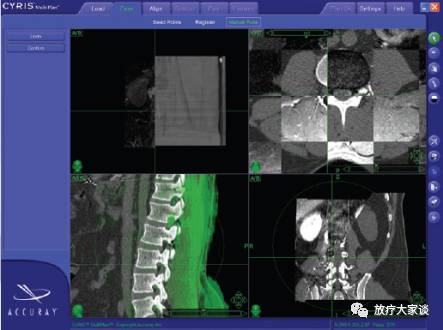

4.13 图像融合

放疗计划系统有哪些放射治疗计划系统(TPS)介绍_https://www.jmylbn.com_新闻资讯_第14张